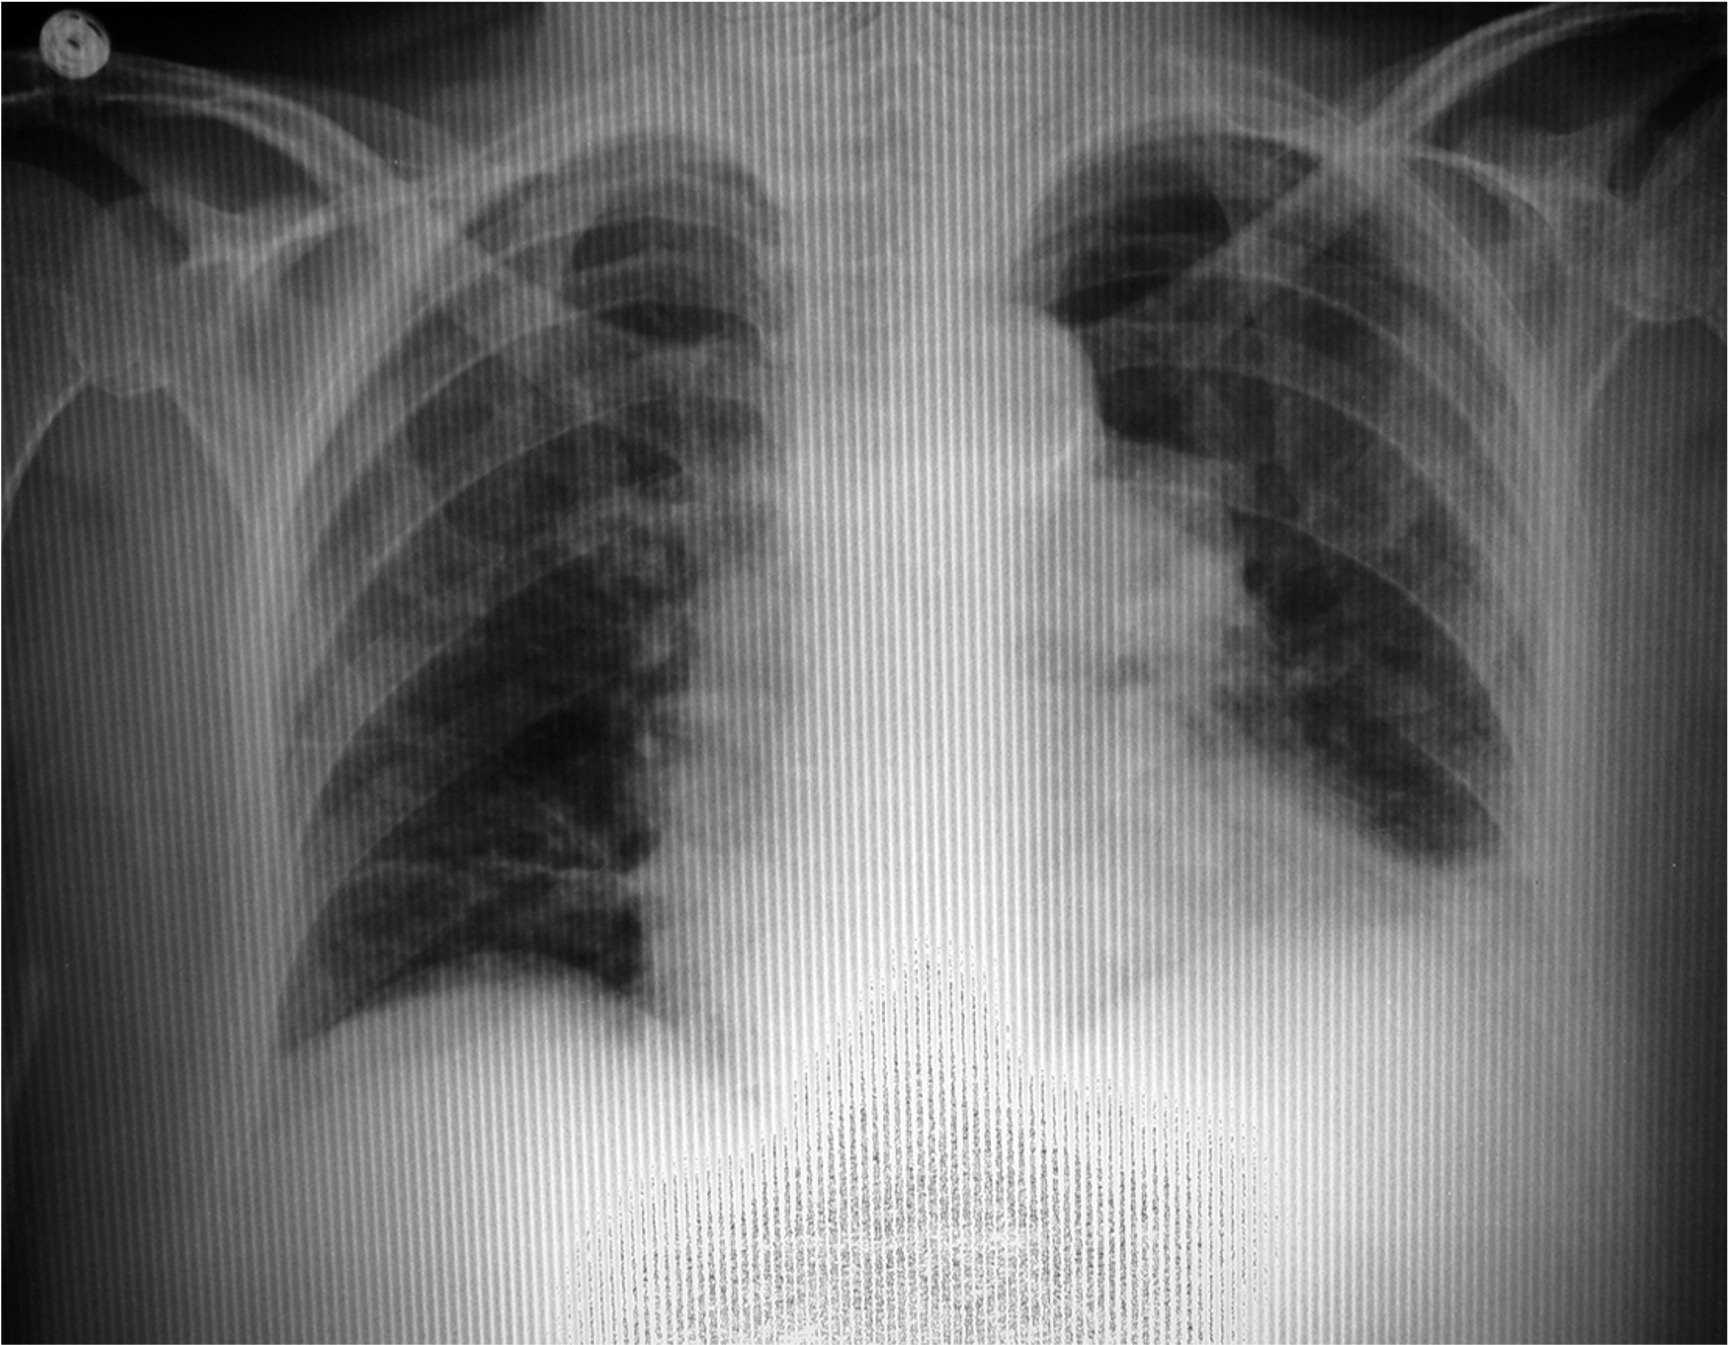

(Image shows saturation - Maybe Big Belly? )